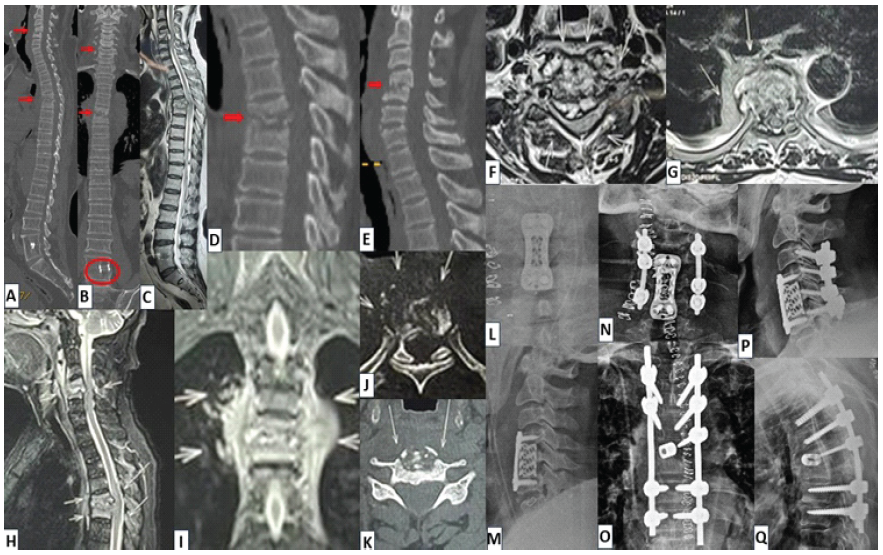

A 43-year-old lady presented with worsening pain over the cervicothoracic region (6 months) and recent-onset weight loss of 7 kg. She was treated by a non-allopathic practitioner for 3 months. Her X-ray revealed a semi-segmented hemivertebra (mixed formation-segmentation defect) at T6-T7. There was significant tenderness at the upper thoracic and thoracolumbar levels. Neurological examination was normal. Imaging studies (X-rays, CT and MRI) suggested a potential diagnosis of MSTB with non-contiguous involvement (T3-T4 spondylodiscitis [with partial destruction of right T4], T9-T10 spondylodiscitis [with T10 left-sided vertebral destruction], large granulation tissue on right and left paravertebral regions at T3-T4 and T10, respectively; and compressive epidural granulation tissue at both levels; Fig. 2a-k). CT-guided biopsy revealed a diagnosis of tubercular granuloma.

Figure 2: (a) Case 2 – radiological findings: Antero-posterior (AP) view of plain thoracolumbar radiograph showing right T6 hemivertebra with T6-T7 mixed formation-segmentation vertebral anomaly, (b) mid-sagittal section of computed tomography (CT) image showing end-plate irregularities at T3-T4 and T9-T10 levels (c and d) CT images – coronal and 3-D reconstruction sequences showing T6-T7 semi-segmented hemi-vertebrae (mixed formation-segmentation vertebral anomaly), (e and f) Sagittal sections-contrast-enhanced magnetic resonance imaging (CE-MRI) showing significant evidence of T3-T4 and T9-T10 spondylodiscitis with large granulation tissue on para-vertebral and pre-vertebral regions, (g and h) axial sections of CE-MRI showing partial destruction of right T4 vertebral body with large granulation tissue, left-sided vertebral destruction at T10 (with abscess/granulation tissue) and compressive epidural granulation tissue at both levels, (i) left para-sagittal section – short tau inversion recovery sequence of MRI showing extensive hyperintensity (S/O granulation tissue) at T9-T10 level, (j) mid-sagittal section of T2WI-MRI showing T3-T4, T9-T10 spondylodiscitis and pre-vertebral granulation tissue/abscess, (k) coronal section of CE-MRI showing para-vertebral granulation tissue at T3-T4 and T9-T10 levels, (l and m) immediate post-operative images showing C6-T12 posterior instrumented stabilisation, laminectomy from T2-T5 and T8-T11 levels, partial corpectomy of T4,T10 and reconstruction using iliac crest bone grafting, (n and o) follow-up plain radiographs-AP and lateral views at 6 months showing good implant position and satisfactory healing.

In view of disease severity, surgical debridement with cord decompression and long-segment instrumented fusion was planned. Considering intervening anomalous vertebrae at T6-7, the patient underwent C6-T12 posterior instrumented stabilisation, laminectomy from T2-T5 and T8-T11, circumferential decompression at T3-T4 and T9-T10 with partial corpectomy of T4 and T10, debridement of unhealthy granulation tissues, reconstruction at corpectomy levels with iliac crest bone graft, followed by posterior fusion with bone graft (at C6-T12; Fig. 2l-o). Tissue HPE, molecular tests and TB culture revealed the diagnosis of tuberculosis (TB). Surgery was followed by 1st-line ATT. She has completed 10 months of therapy, demonstrated clinical and radiological healing, and now remains stable with 16 months of follow-up.

Another similar multilevel (cervical and thoracic) TB (biopsy-proven) in a 74-year-old male (with multiple comorbidities – diabetes, coronary artery disease and renal disease) is presented in Fig. 3. He had severe myelopathy and neurodeficit at presentation (Frenkel-C). The patient had a successful recovery after adequate chemotherapy for 11 months and was clinically stable with 14 months of follow-up.

Figure 3: (a and b) Case 3 – radiological findings: Para-sagittal and coronal computed tomography (CT) images (of whole spine) showing destruction at C4-C5 and T5-T6 vertebral levels (evidence of previous surgery at L4-L5 level with interbody metallic cage), (c) mid-sagittal section of whole spine T2WI-magnetic resonance imaging (MRI) showing large epidural abscess at C4-C5 and T5-T6 levels with severe compression over spinal cord, (d and e) mid-sagittal CT sections showing destruction at C4-C5 and T5-T6 levels, suggestive of possible spondylodiscitis, (f and g) axial sections of T2WI-MRI showing large epidural abscesses with severe compression over spinal cord at C4-C5 and T5-T6 levels, (h) mid-sagittal sections of CE-MRI showing pre-/para-vertebral and large epidural abscess at C4-C5 and T5-T6 levels, (i) mid-coronal sections of short tau inversion recovery sequence on MRI showing large paravertebral abscess/granulation tissue at T5-T6 level, (j and k) axial sections of CT imaging showing severe bone destruction of T5 and C5 vertebral bodies, (l and m) stage 1: Post-operative AP and lateral radiographs showing C5 corpectomy with spinal decompression and C4-C5 fusion with Harm’s cage-plate construct, (n-q) stage 2: Post-operative radiographs showing the final constructs at the cervical and thoracic levels (360° fusion constructs).